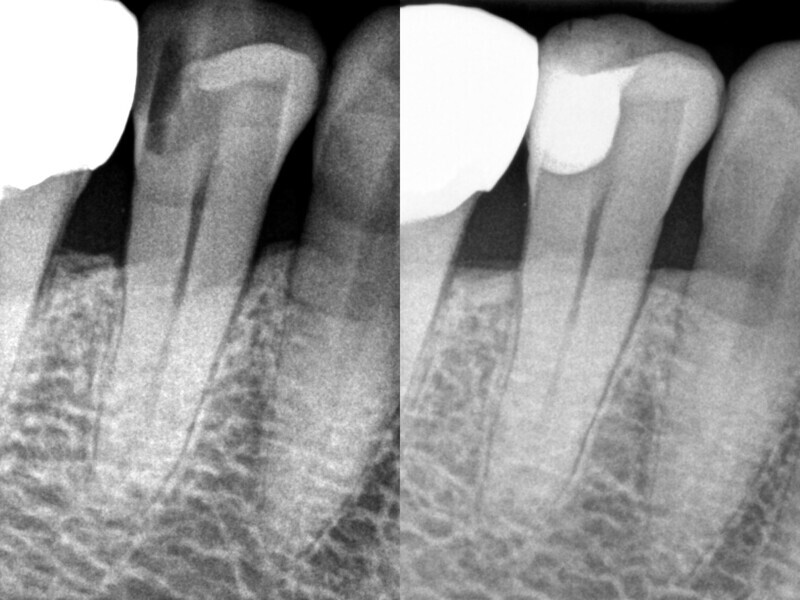

La comparaison des radiographies pré et postopératoires montre la qualité du traitement (Fig. 23). Grâce aux excellentes propriétés d’application du composite thermovisqueux, la restauration ne contient aucune bulle d’air. De plus, il existe une uniformité entre les deux composites utilisés en termes de visibilité aux rayons X et dans l’ensemble, la restauration apparait homogène, sans transitions visibles entre le composite de base flow et le composite de remplissage bulk. La radiographie préopératoire n’a pas permis de montrer toute l’étendue de la lésion. Ce n’est qu’au cours d’un traitement qu’il est devenu évident qu’une préparation très approfondie devait être effectuée afin d’éliminer complètement la structure dentaire affectée. Afin de maintenir la vitalité de la pulpe, une densibilisation a été réalisée avant la restauration composite proprement dite.